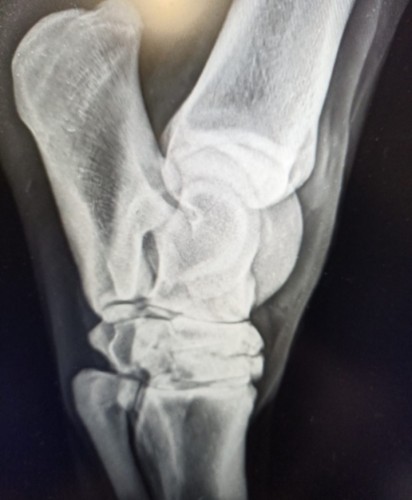

Anonymní: Dobrý den,mohu se prosím zeptat,rozumí tady někdo snímků z rtg. Konik prý má artrózou v zadní noze. Zajímalo by mě ,jak moc je ta artroza rozsáhlá. Budu ráda za názory

Chýva tam miestami kĺbna štrbina - takže závažná je celkom dosť (nie som ortopéd), ale to je iba snímok, neliečime snímok, ale zviera- teda snímky (hocaké výsledky) vždy v kontexte ako kôň vyzerá, koľko má rokov, ako chodí, načo ho chcete využívať a čo viete /chcete /môžte-neviete /nechcete /nemôžte poskytnúť.

Horsana:Chýva tam miestami kĺbna štrbina - takže závažná je celkom dosť (nie som ortopéd), ale to je iba snímok, neliečime snímok, ale zviera- teda snímky (hocaké výsledky) vždy v kontexte ako kôň vyzerá, koľko má rokov, ako chodí, načo ho chcete využívať a čo viete /chcete /môžte-neviete /nechcete /nemôžte poskytnúť.